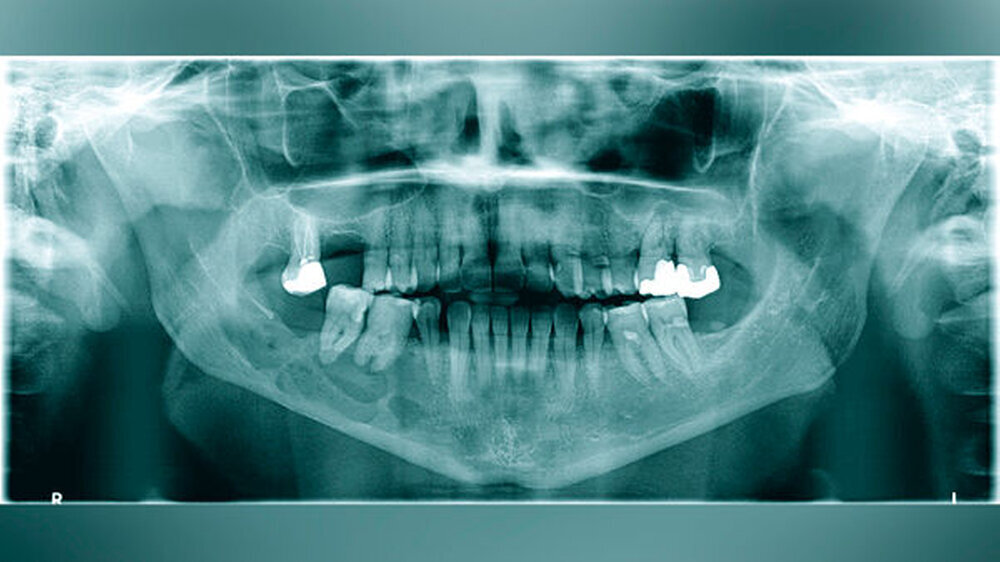

Eine 57-jährige Patientin stellte sich mit einer seit dem Vortag zunehmenden Schwellung des rechten Unterkiefers in der Klinik und Poliklinik für Mund-, Kiefer- und Gesichtschirurgie der Universitätsmedizin Mainz vor. Vier Monate zuvor habe sich der Zahn 47 gelockert, woraufhin sich die Frau bei ihrem Hauszahnarzt zur Abklärung vorgestellt hatte. In der durchgeführten Panoramaschichtaufnahme zeigte sich ein multizystisch anmutender Befund von regio 45 bis in den aufsteigenden Unterkieferast reichend (Abbildung 1). Die Patientin entschied sich jedoch im Nachgang aufgrund der subjektiv fehlenden klinischen Symptomatik – entgegen der Empfehlung des Hauszahnarztes – gegen eine zeitnahe Vorstellung in der Mund-, Kiefer- und Gesichtschirurgie.

Aufgrund des klinisch unklaren Lokalbefunds in Zusammenschau mit dem radiologischen Befund wurde die Indikation zur Durchführung einer Digitalen Volumentomografie gestellt. Diese bestätigte eine von regio 45 bis in den aufsteigenden Unterkieferast reichende, etwa 6,5 cm lange zystische Läsion mit partieller Auflösung der Kortikalis. Die Wurzeln der sich in der Läsion befindlichen Zähne 47 und 46 wiesen keine Anzeichen einer Resorption auf. Innerhalb der Läsion waren knöcherne Septen zu erkennen, die auf einen multizystischen Prozess hinwiesen (Abbildung 2).